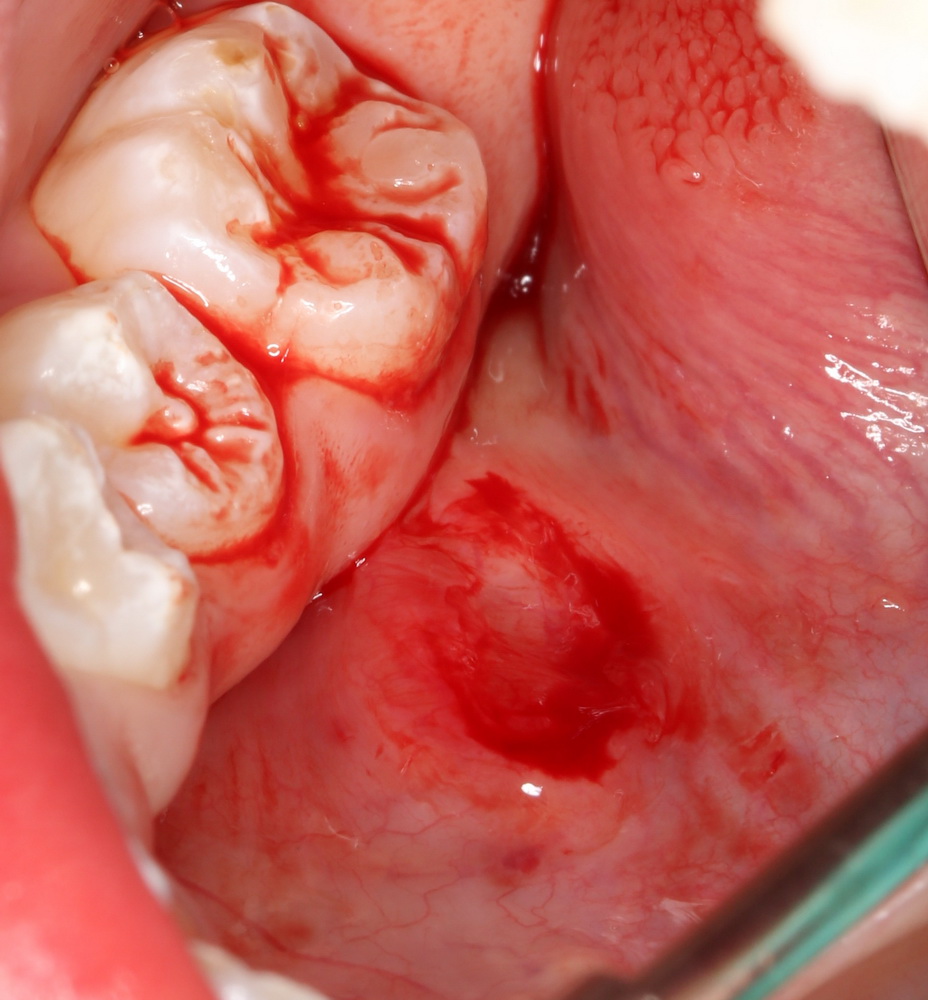

Сначала аккуратно удаляется верхняя часть часть кисты, ее крыша. Для этого киста рассекается ножницами, удаляется ее содержимое, а образовавшийся мешок просто отрезается почти заподлицо:

Затем рана промывается и край оболочки кисты сшивается со слизистой оболочкой:

Для этого нужен очень тонкий шовный материал и микрохирургические инструменты. В данном случае мы использовали Prolene 7-0. Теперь понимаете, почему без оптики — никак?

Тут есть нюанс. В данном случае всё просто. Но иногда дно ранулы находится глубоко в толще тканей, и физически невозможно вывести его «в ноль» со слизистой. В подобных ситуациях оболочка кисты рассекается и подшивается на уровне окружающей слизистой, а полость кисты, которая теперь стала просто углублением, заполняется йодоформной турундой или губкой. Ну, или можно метрогилом-солкосерилом-вазелином заполнить. Главное, чтобы не слиплись края).

Всё. Операция закончена. От момента анестезии до последней лигатуры — не более 10 минут. Скажите, ради этого стоило госпитализироваться со всеми вытекающими?